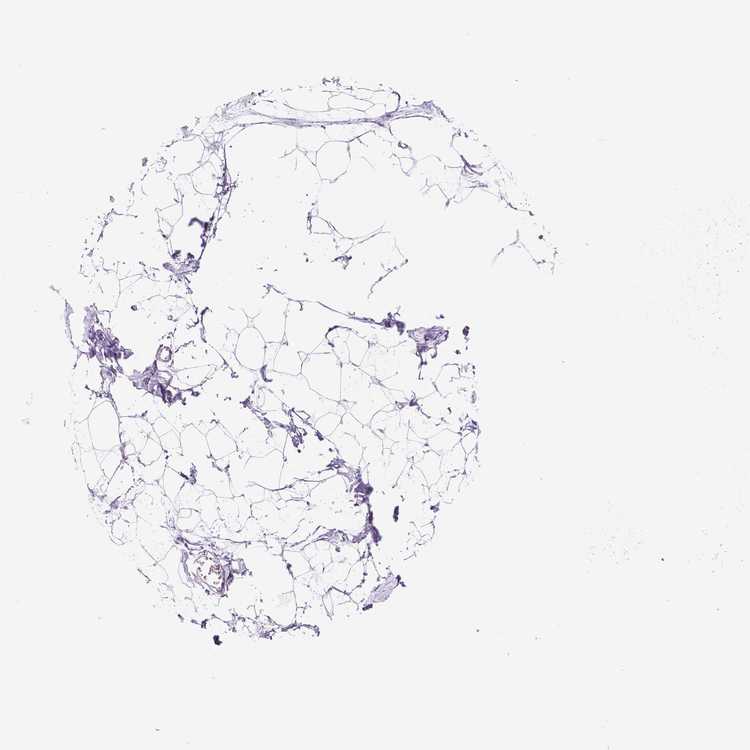

TISSUE PRIMARY DATA BREAST Show tissue menu

BREAST - Antibody stainingi

Antibody staining in the annotated cell types in the current human tissue is reported as not detected, low, medium, or high, based on conventional immunohistochemistry profiling in selected tissues. This score is based on the combination of the staining intensity and fraction of stained cells.

Each image is clickable and will lead to virtual microscopy that enables deeper exploration of all samples and also displays staining intensity scores, fraction scores and subcellular localization as well as patient and tissue information for each sample.

Antibody HPA001936

Adipocytes Not detected

Glandular cells Not detected

Myoepithelial cells Not detected